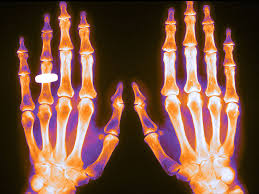

Pérdida ósea en pacientes con enfermedad musculoesquelética reumática inflamatoria tratados con dosis bajas de glucocorticoides y prevención con medicamentos contra la osteoporosis

Las dosis de glucocorticoides tan bajas como 2,5 mg/día se asociaron con la pérdida de densidad mineral ósea (DMO) en pacientes con enfermedades musculoesqueléticas reumáticas inflamatorias (EMRi), pero este efecto se pudo prevenir. La pérdida de DMO en pacientes que recibieron ≥5 mg/día no se previno por completo con los medicamentos contra la osteoporosis que se usan actualmente en la práctica clínica, lo que resultó en un mayor riesgo de fractura. Arthritis Rheumatol, 24 de abril de 2023